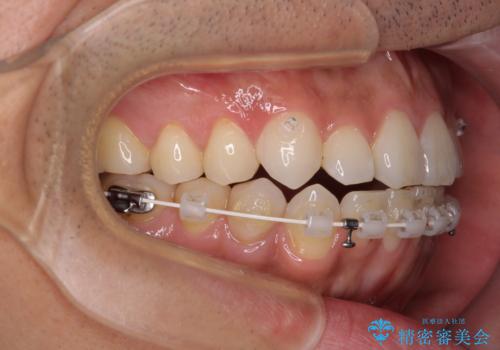

目立たない装置でデコボコを改善 ハーフリンガルによる矯正治療

- 30代男性

- 矯正装置

- ハーフリンガル

- 治療期間

- 1年4ヶ月

- 上下顎歯列のデコボコを改善したいとのことで来院された患者様です。

自己管理の大変なインビザラインや、目立つ表側のワイヤー矯正は避けたいとのことで、

上顎だけ裏側装置のハーフリンガルにて矯正しました。

一年と数か月で矯正を終えることができました。

下顎前歯部には後戻り防止のワイヤーを装着しています。